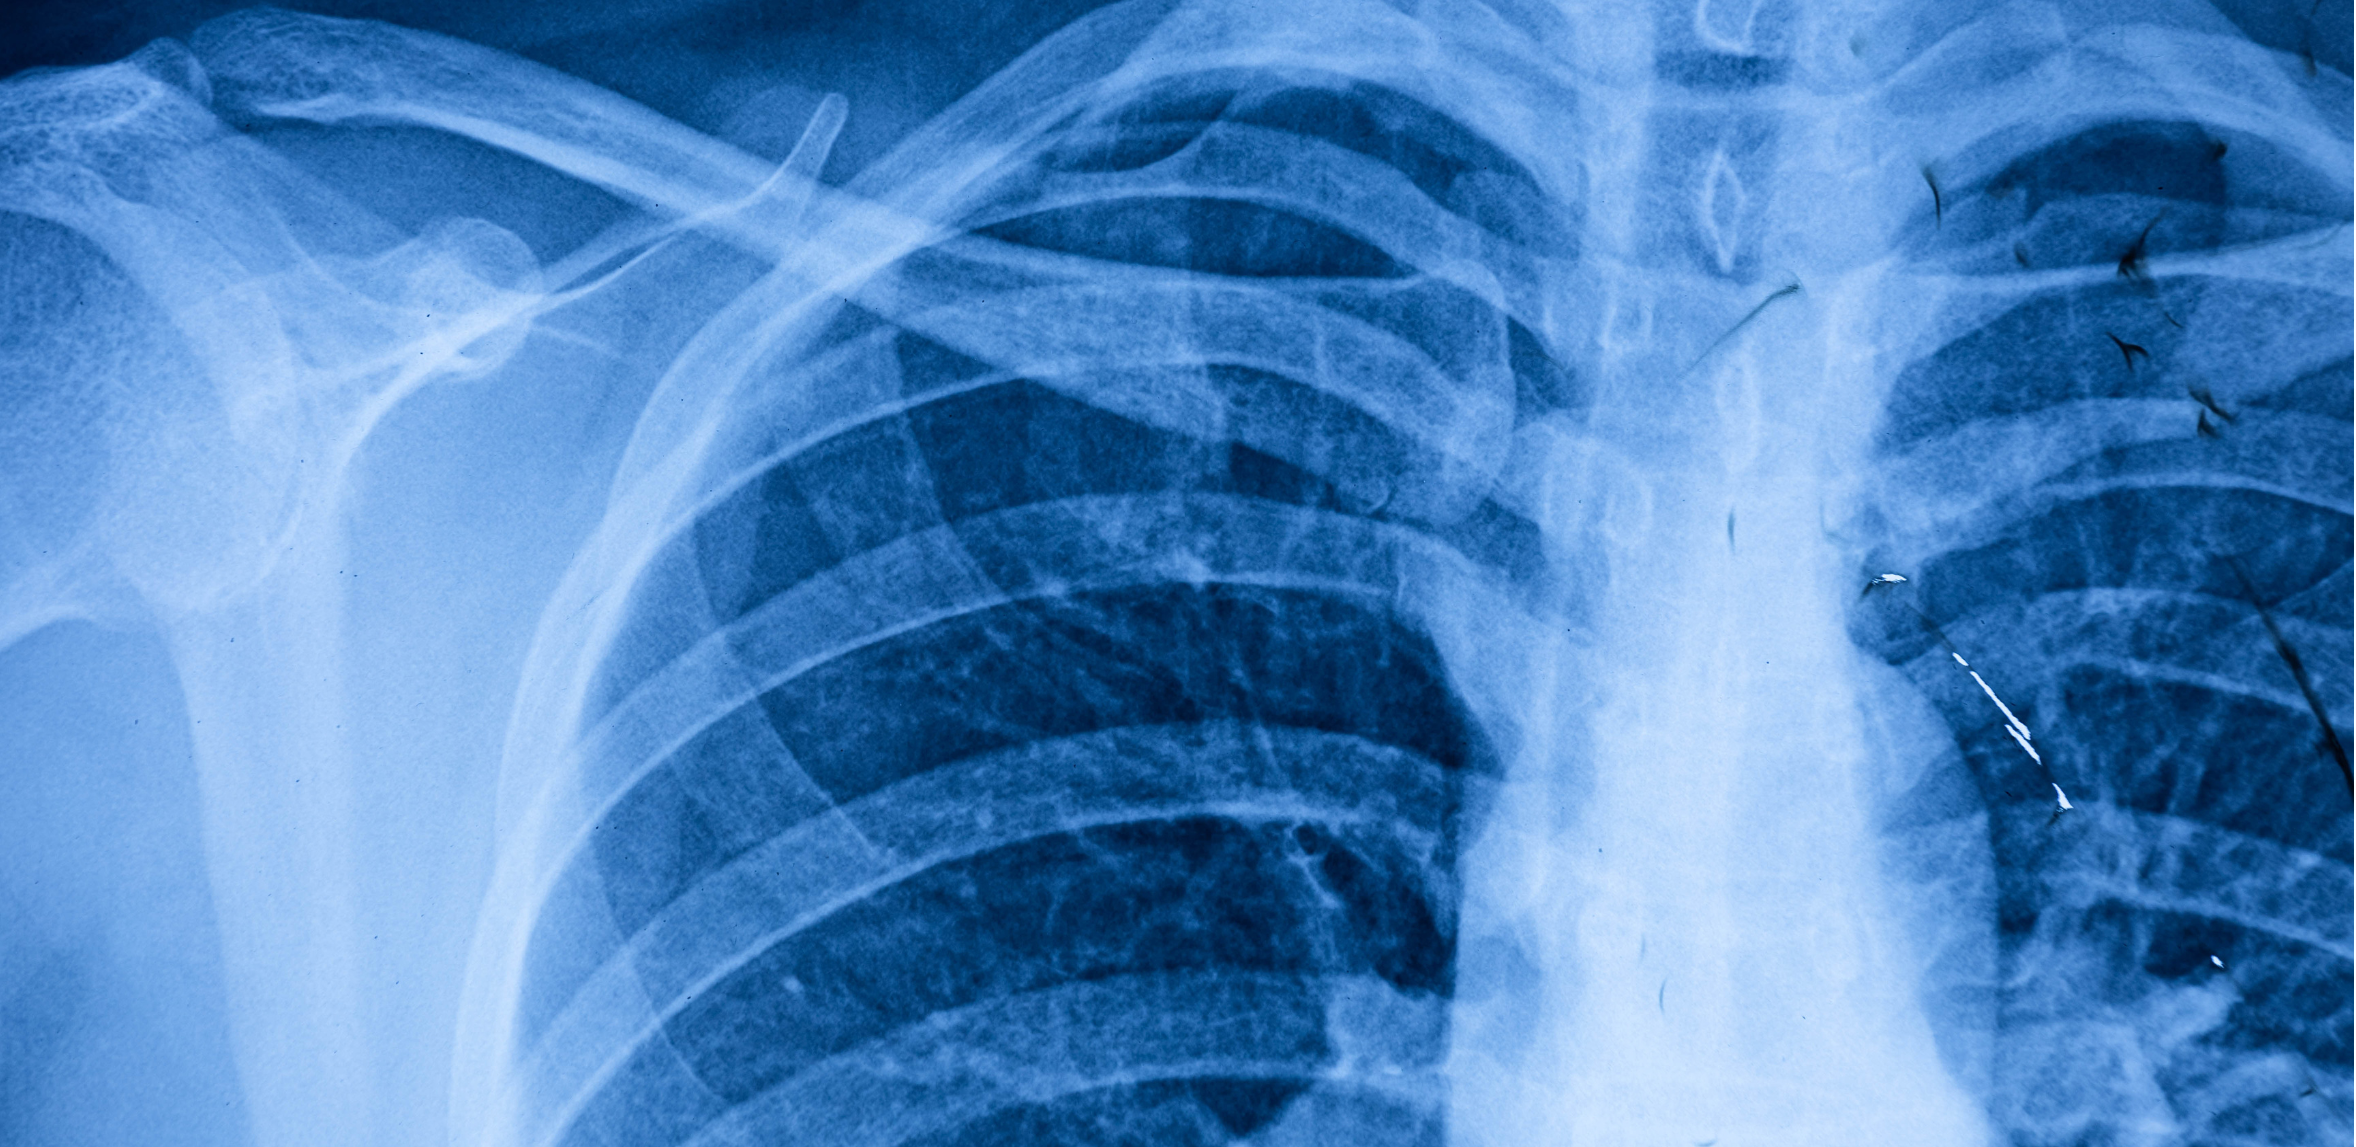

Les tumeurs rares en oncologie thoracique Les cancers bronchiques (non) à petites cellules représentent la majorité des tumeurs prises en charge en oncologie thoracique. Cependant, des pathologies cancéreuses constituent des entités souvent peu connues, parentes pauvres de la recherche clinique. Les mésothéliomes pleuraux, moins de 300 cas par an en Belgique, sont bien connus. Même si les inhibiteurs de point de contrôle immunitaire ont démontré une activité certaine, des approches innovantes indispensables sont en cours d’évaluation. Les approches thérapeutiques des thymomes, que nous devons désormais catégoriser comme des cancers, nécessitent une expertise multidisciplinaire intégrant des traitements locaux même pour des stades métastatiques. Enfin, les traitements des cancers neuroendocrines, tumeurs carcinoïdes et carcinbomes neuroendocrines à grandes cellules, restent complexes et mal définis. Le but de cette journée est de mettre à jour les connaissances et les prises en charge thérapeutiques de ces maladies qui, quoi que rares, touchent chaque année un nombre considérable de personnes.

Les tumeurs rares en oncologie thoracique